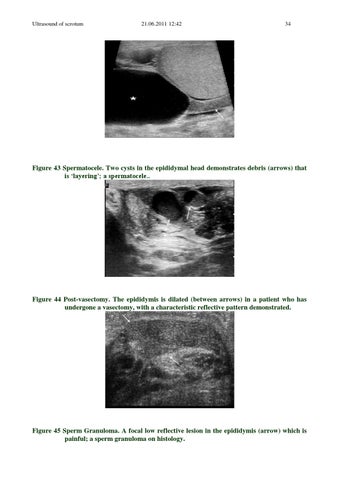

Figure 43 Spermatocele. Two cysts in the epididymal head demonstrates debris (arrows) that is ‘layering’; a spermatocele..

Figure 44 Post-vasectomy. The epididymis is dilated (between arrows) in a patient who has undergone a vasectomy, with a characteristic reflective pattern demonstrated.

Figure 45 Sperm Granuloma. A focal low reflective lesion in the epididymis (arrow) which is painful; a sperm granuloma on histology.